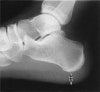

6~8주 정도의 보존적 치료로도 좋아지지 않을 때, 전신 증상, 휴식 시에도 통증이 있는 경우는 선 자세에서 lateral view X-ray 검사를 합니다.

환자의 약 50%에서 족저근막의 바로 위층에 위치한 짧은 굽힘근(flexor brevis)의 기시부에 발꿈치 골극(heel spur; enthesophyte)가 발생하나 통증의 근원은 아닙니다(족저근막염이 없는 성인의 20%가 골극이 있습니다).

X-ray : 족저근막염(Plantar fasciitis)

Heel-Pad Measurement